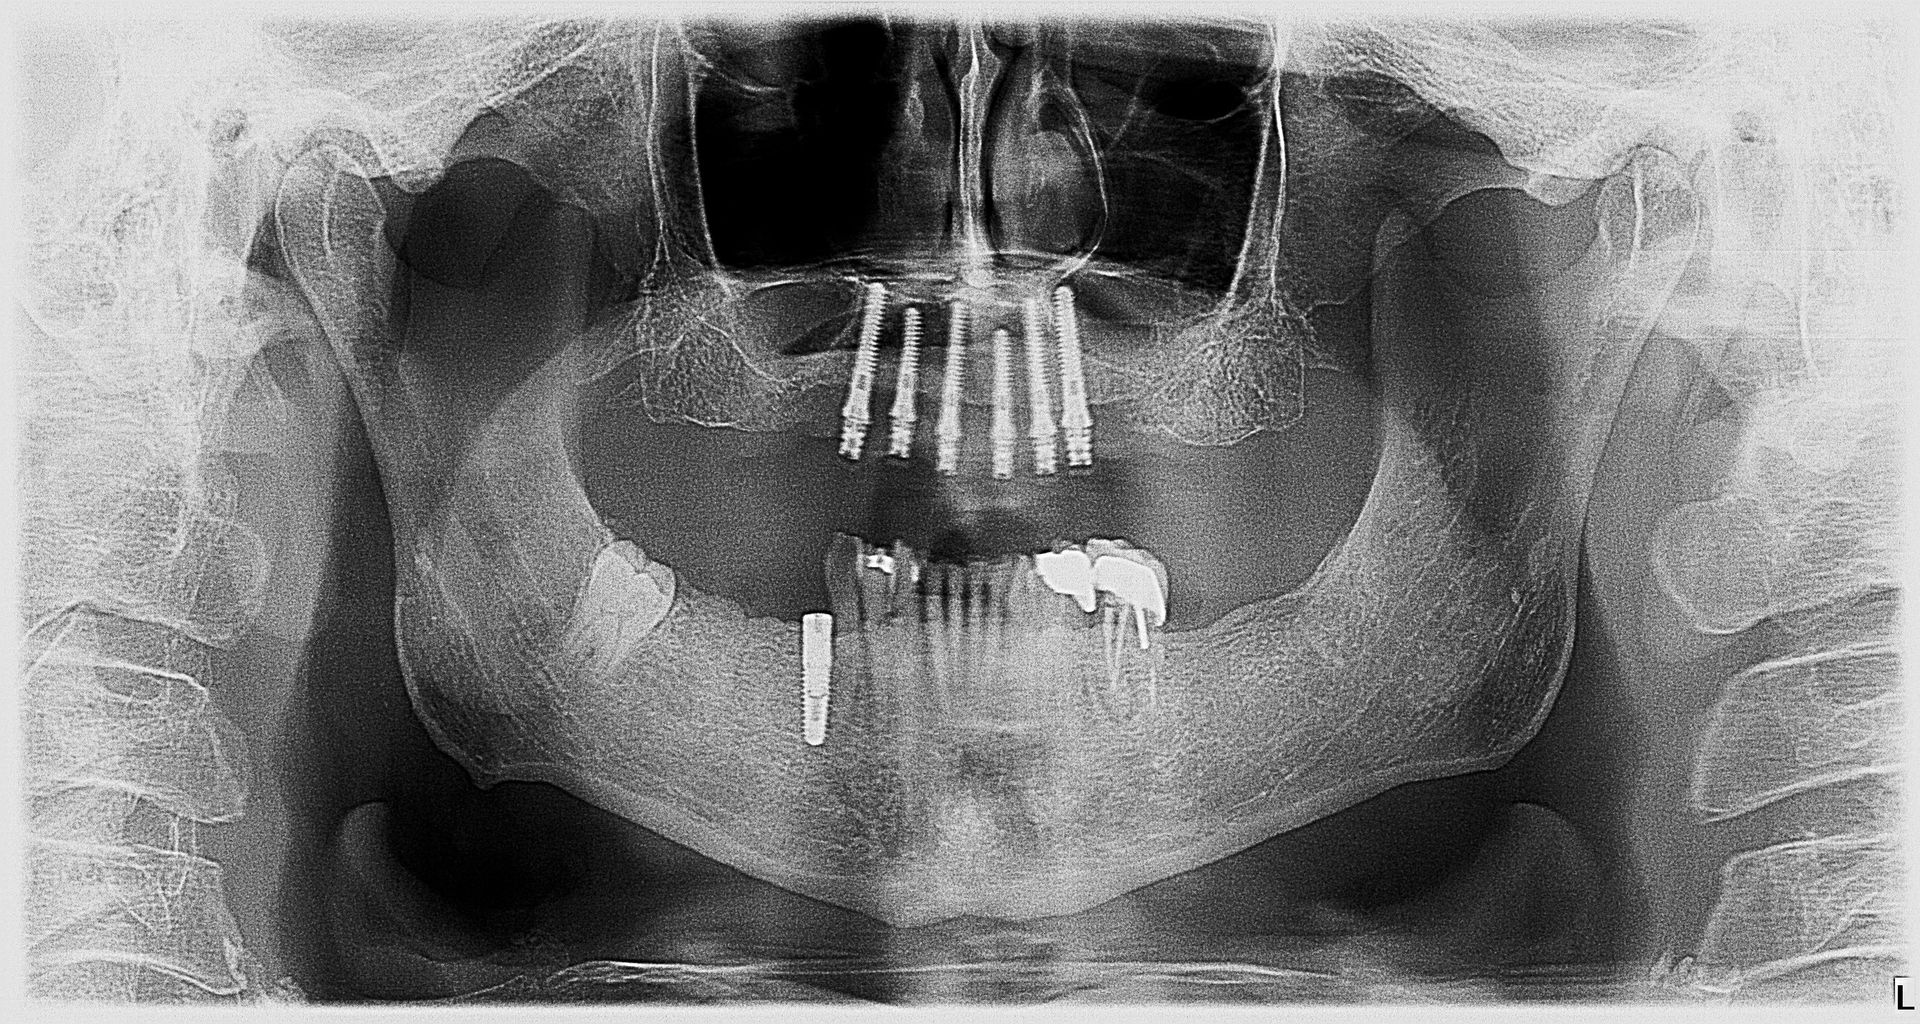

• We do “FULL MOUTH IMPLANT RECONSTRUCTION”

- Implants

- Mini dental implants

- Full mouth implant reconstruction

- Camlog implant placement